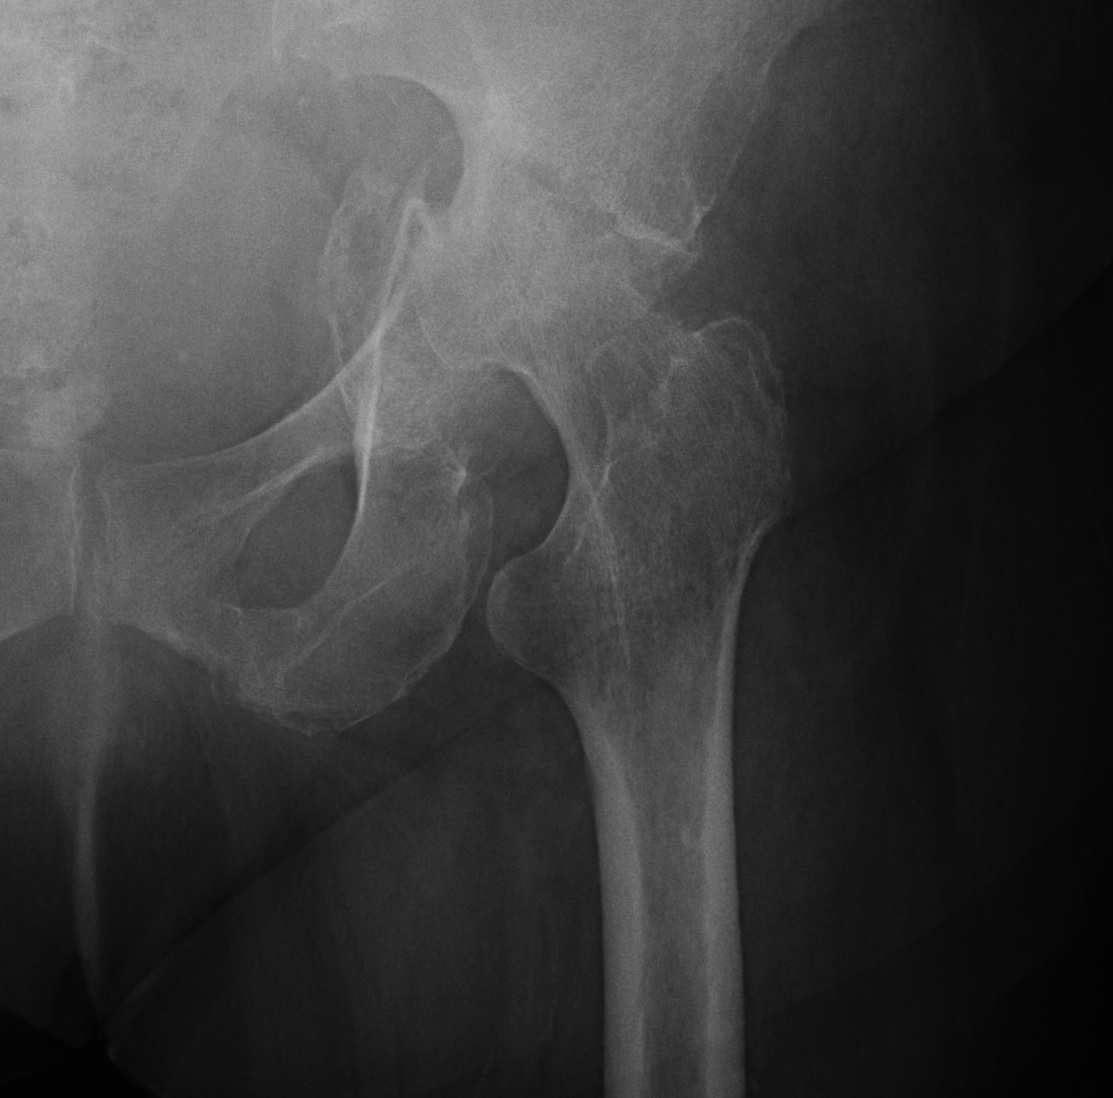

SUFE Perthes

DDH Protrusio

Trauma

Paget's AVN